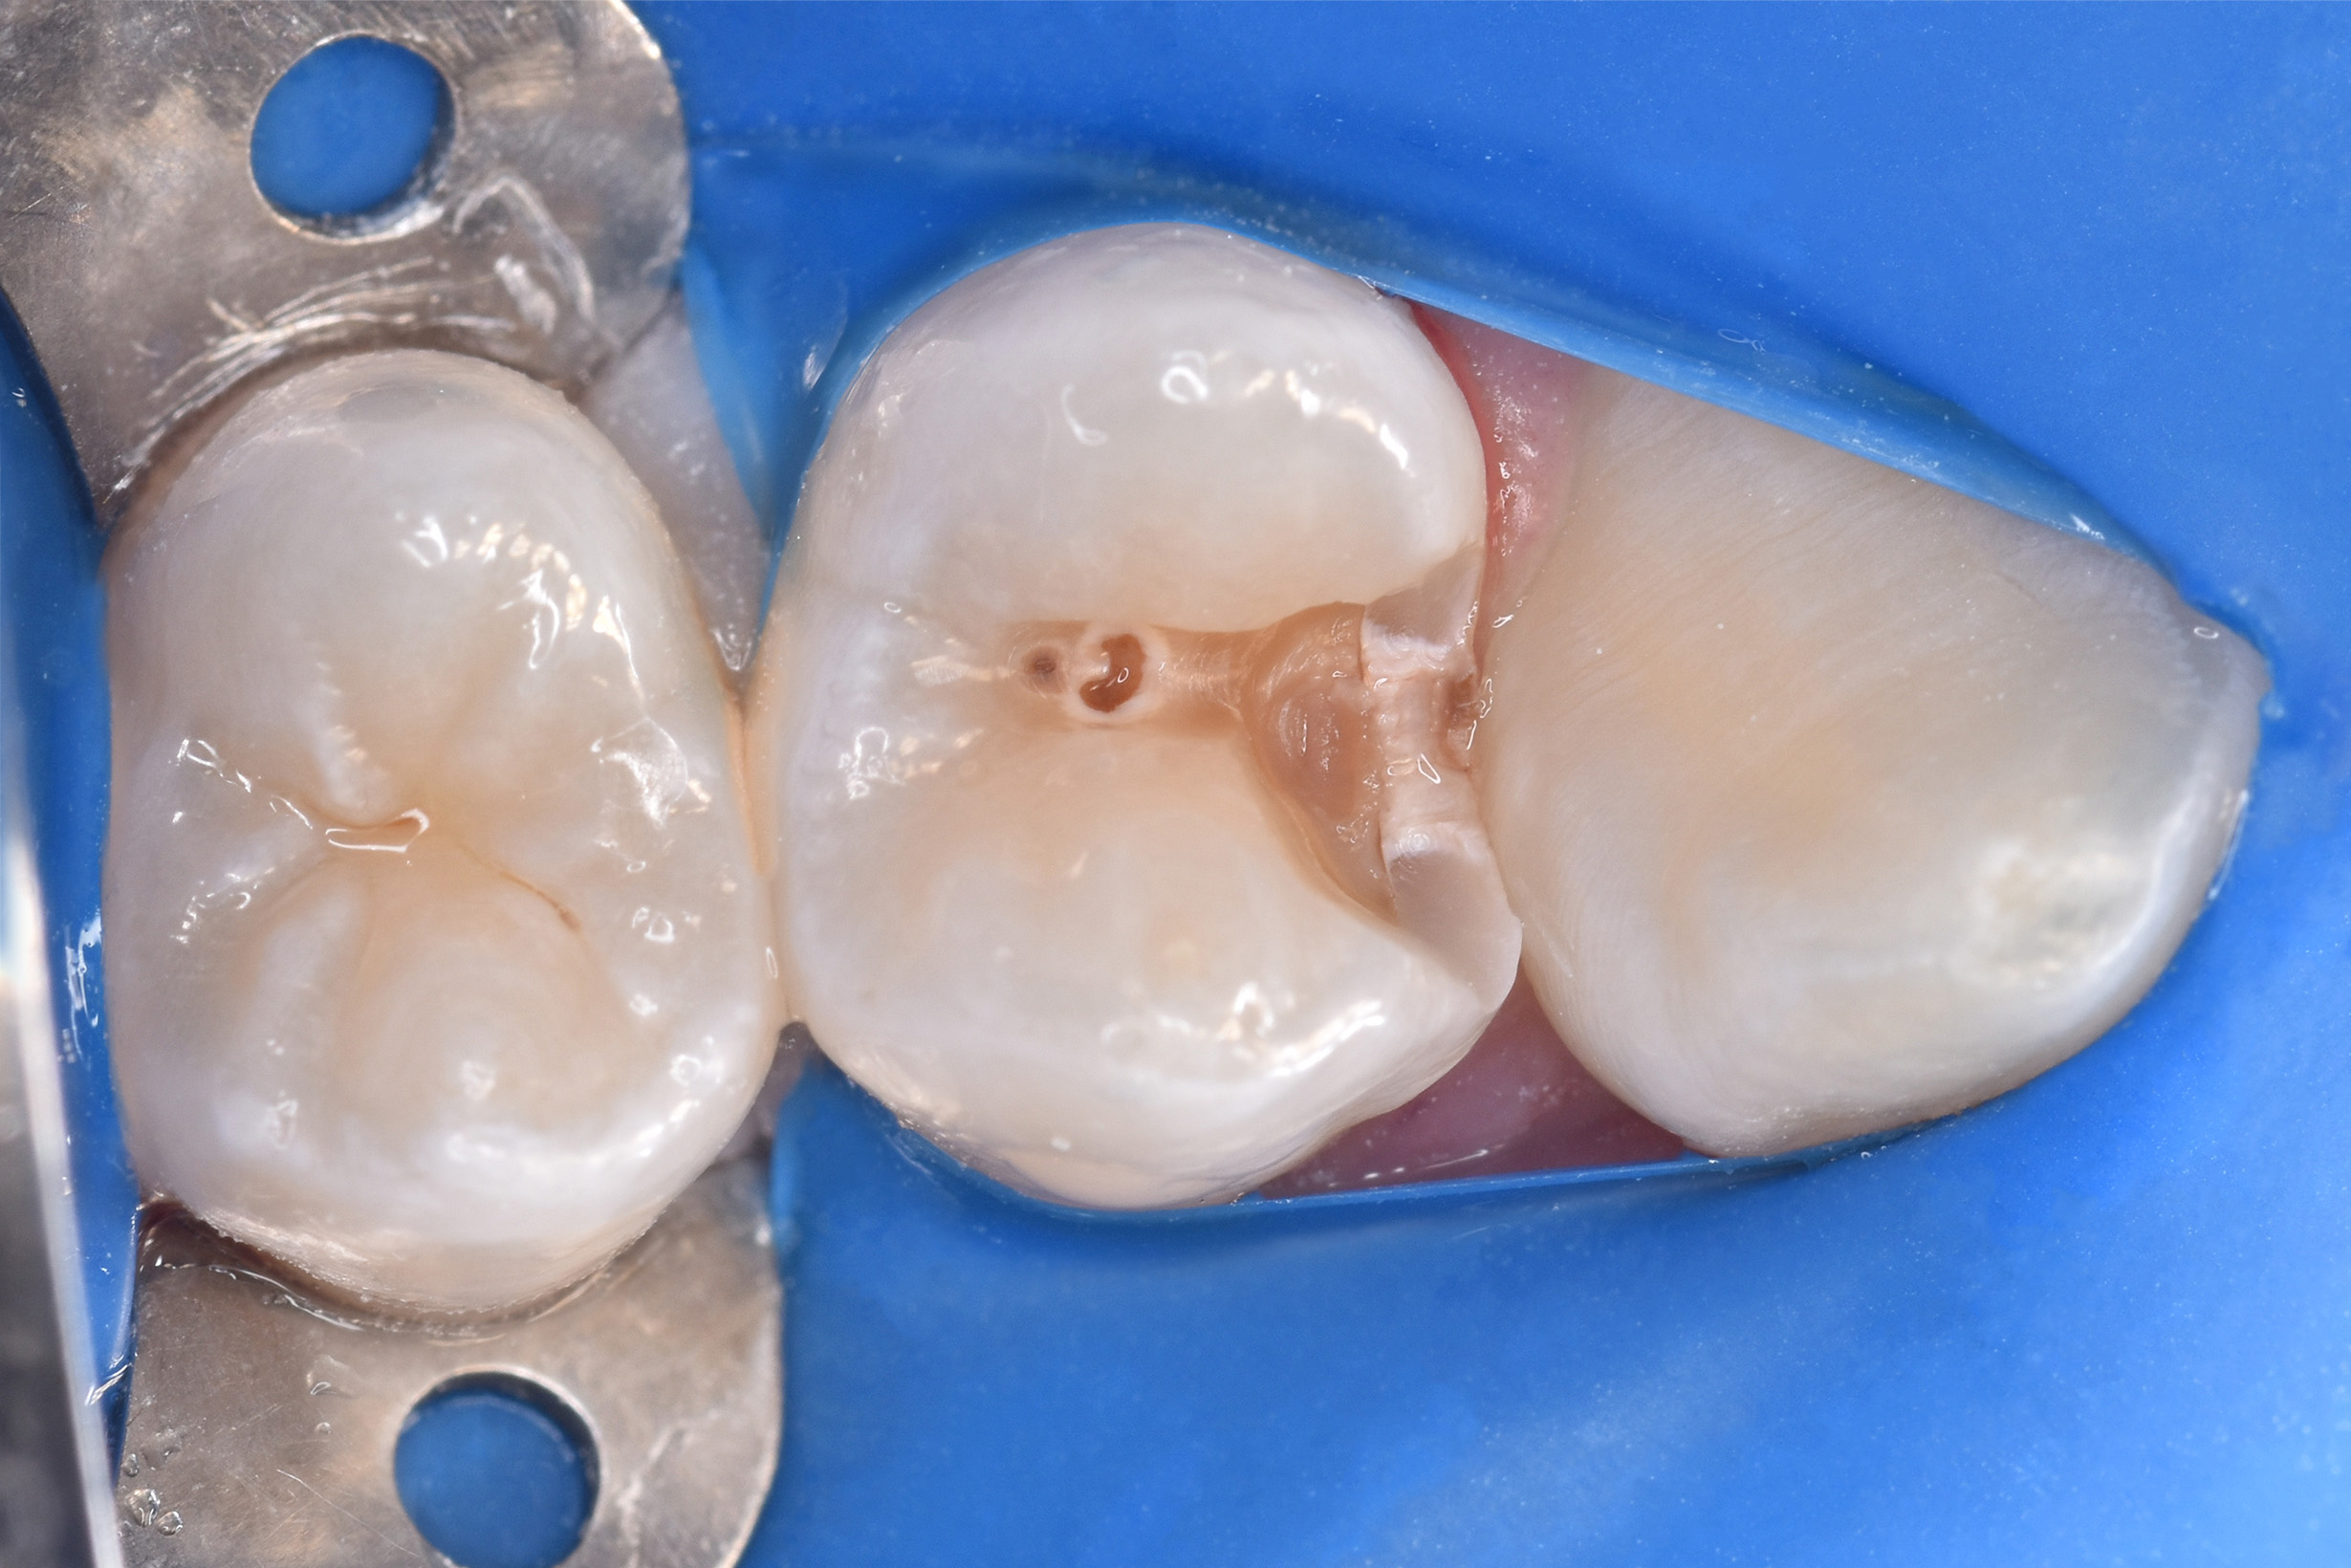

Пациент 12 лет. На осмотре выявлена кариозная полость, жалоб не было. Скрытые кариозные процессы на контактных поверхностях – частая проблема в подростковом возрасте. Рекомендовано не пропускать плановые профосмотры и проф. гигиены полости рта, а так же с 14 лет – КТ раз в год минимум для расширенной диагностики.

Пролечен контактный кариес, реставрация пломбировочным материалом